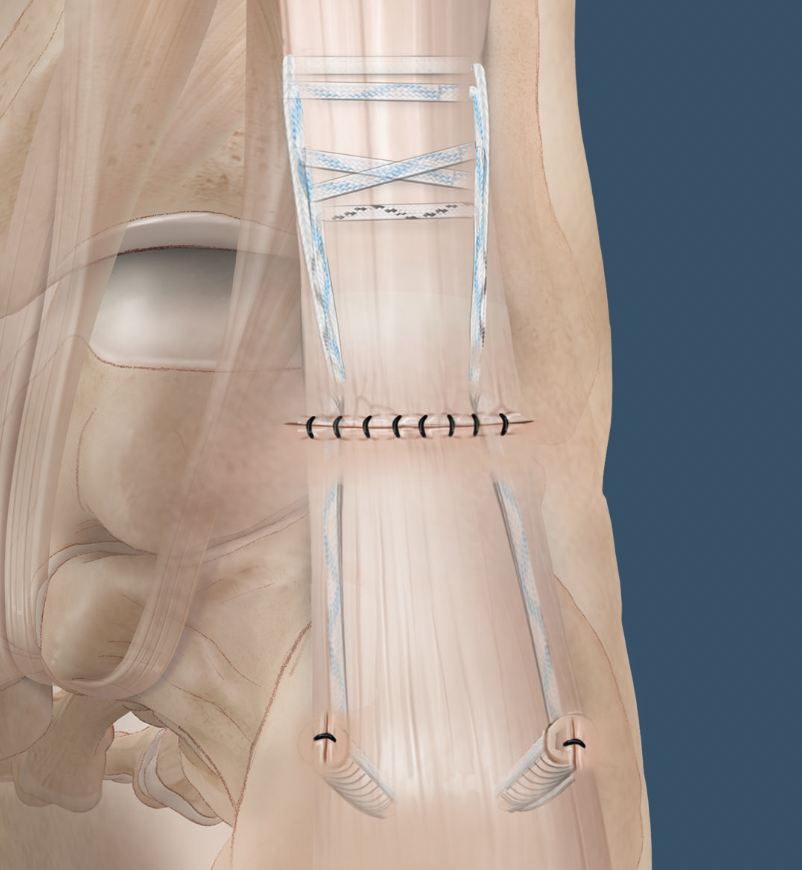

Minimally invasive repair

Percutaneous suture technique

Arthrex PARS

Calcaneal anchor technique

Arthrex Speedbridge technique

Turndown + FHL transfer with FHL passed through a transverse tunnel in the calcaneum

FHL transfer

Technique

Identify FHL tendon medially

- identify and protect tibial nerve

- pull tendon through and transect with sufficient length

- through drill hole in calcaneum and secure